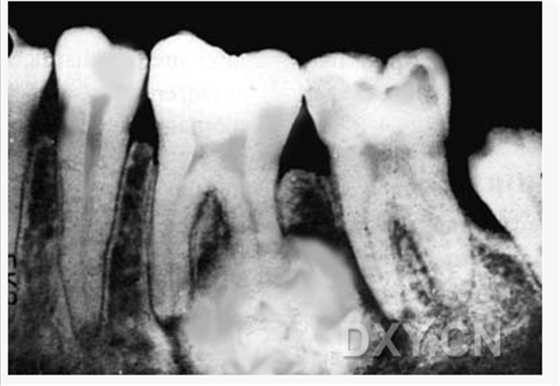

舍格倫綜合征

鼻腭囊腫

頜骨骨折

頜骨術(shù)后囊腫

牙源性角化囊腫

骨囊腫

良性成牙骨質(zhì)細(xì)胞瘤